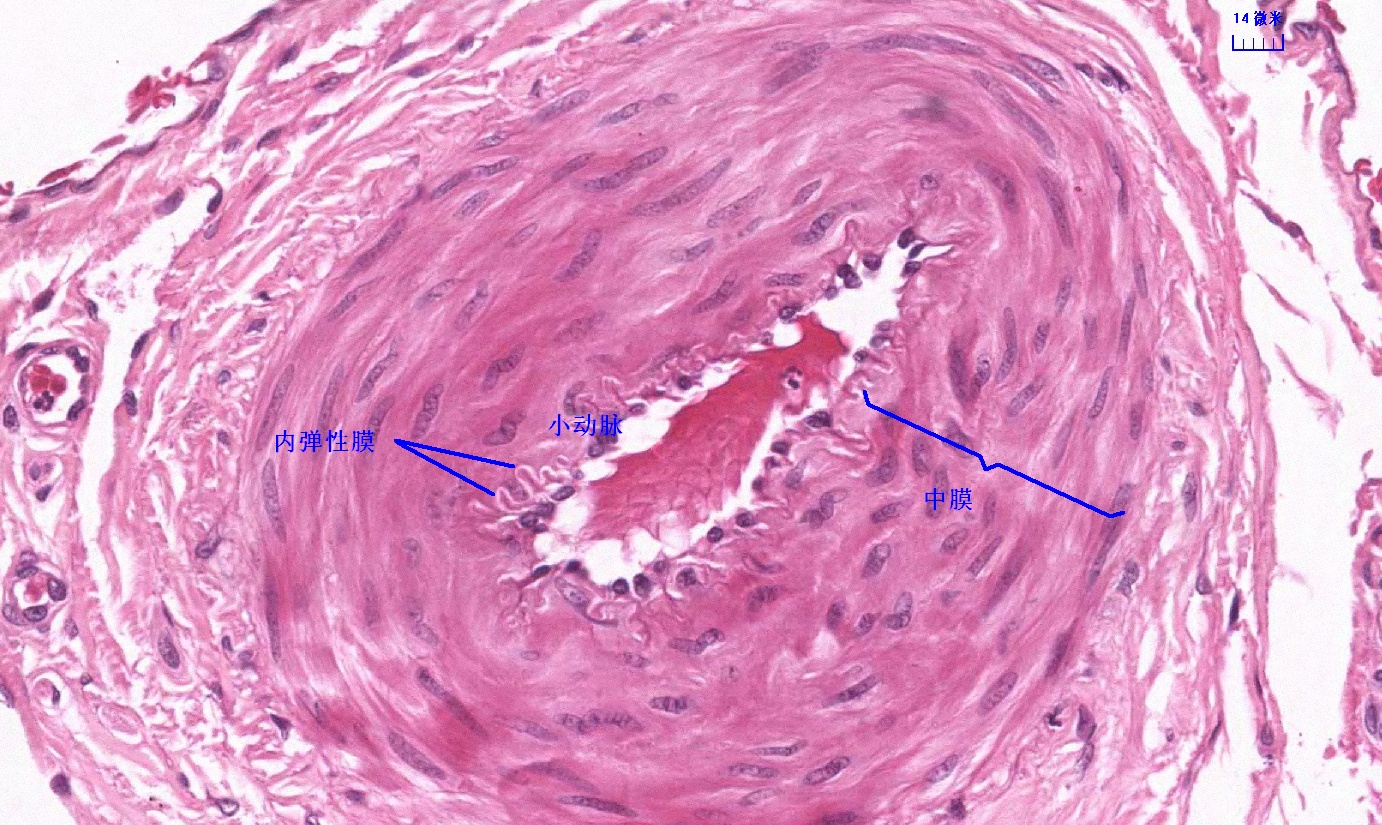

6.1 循环系统切片库